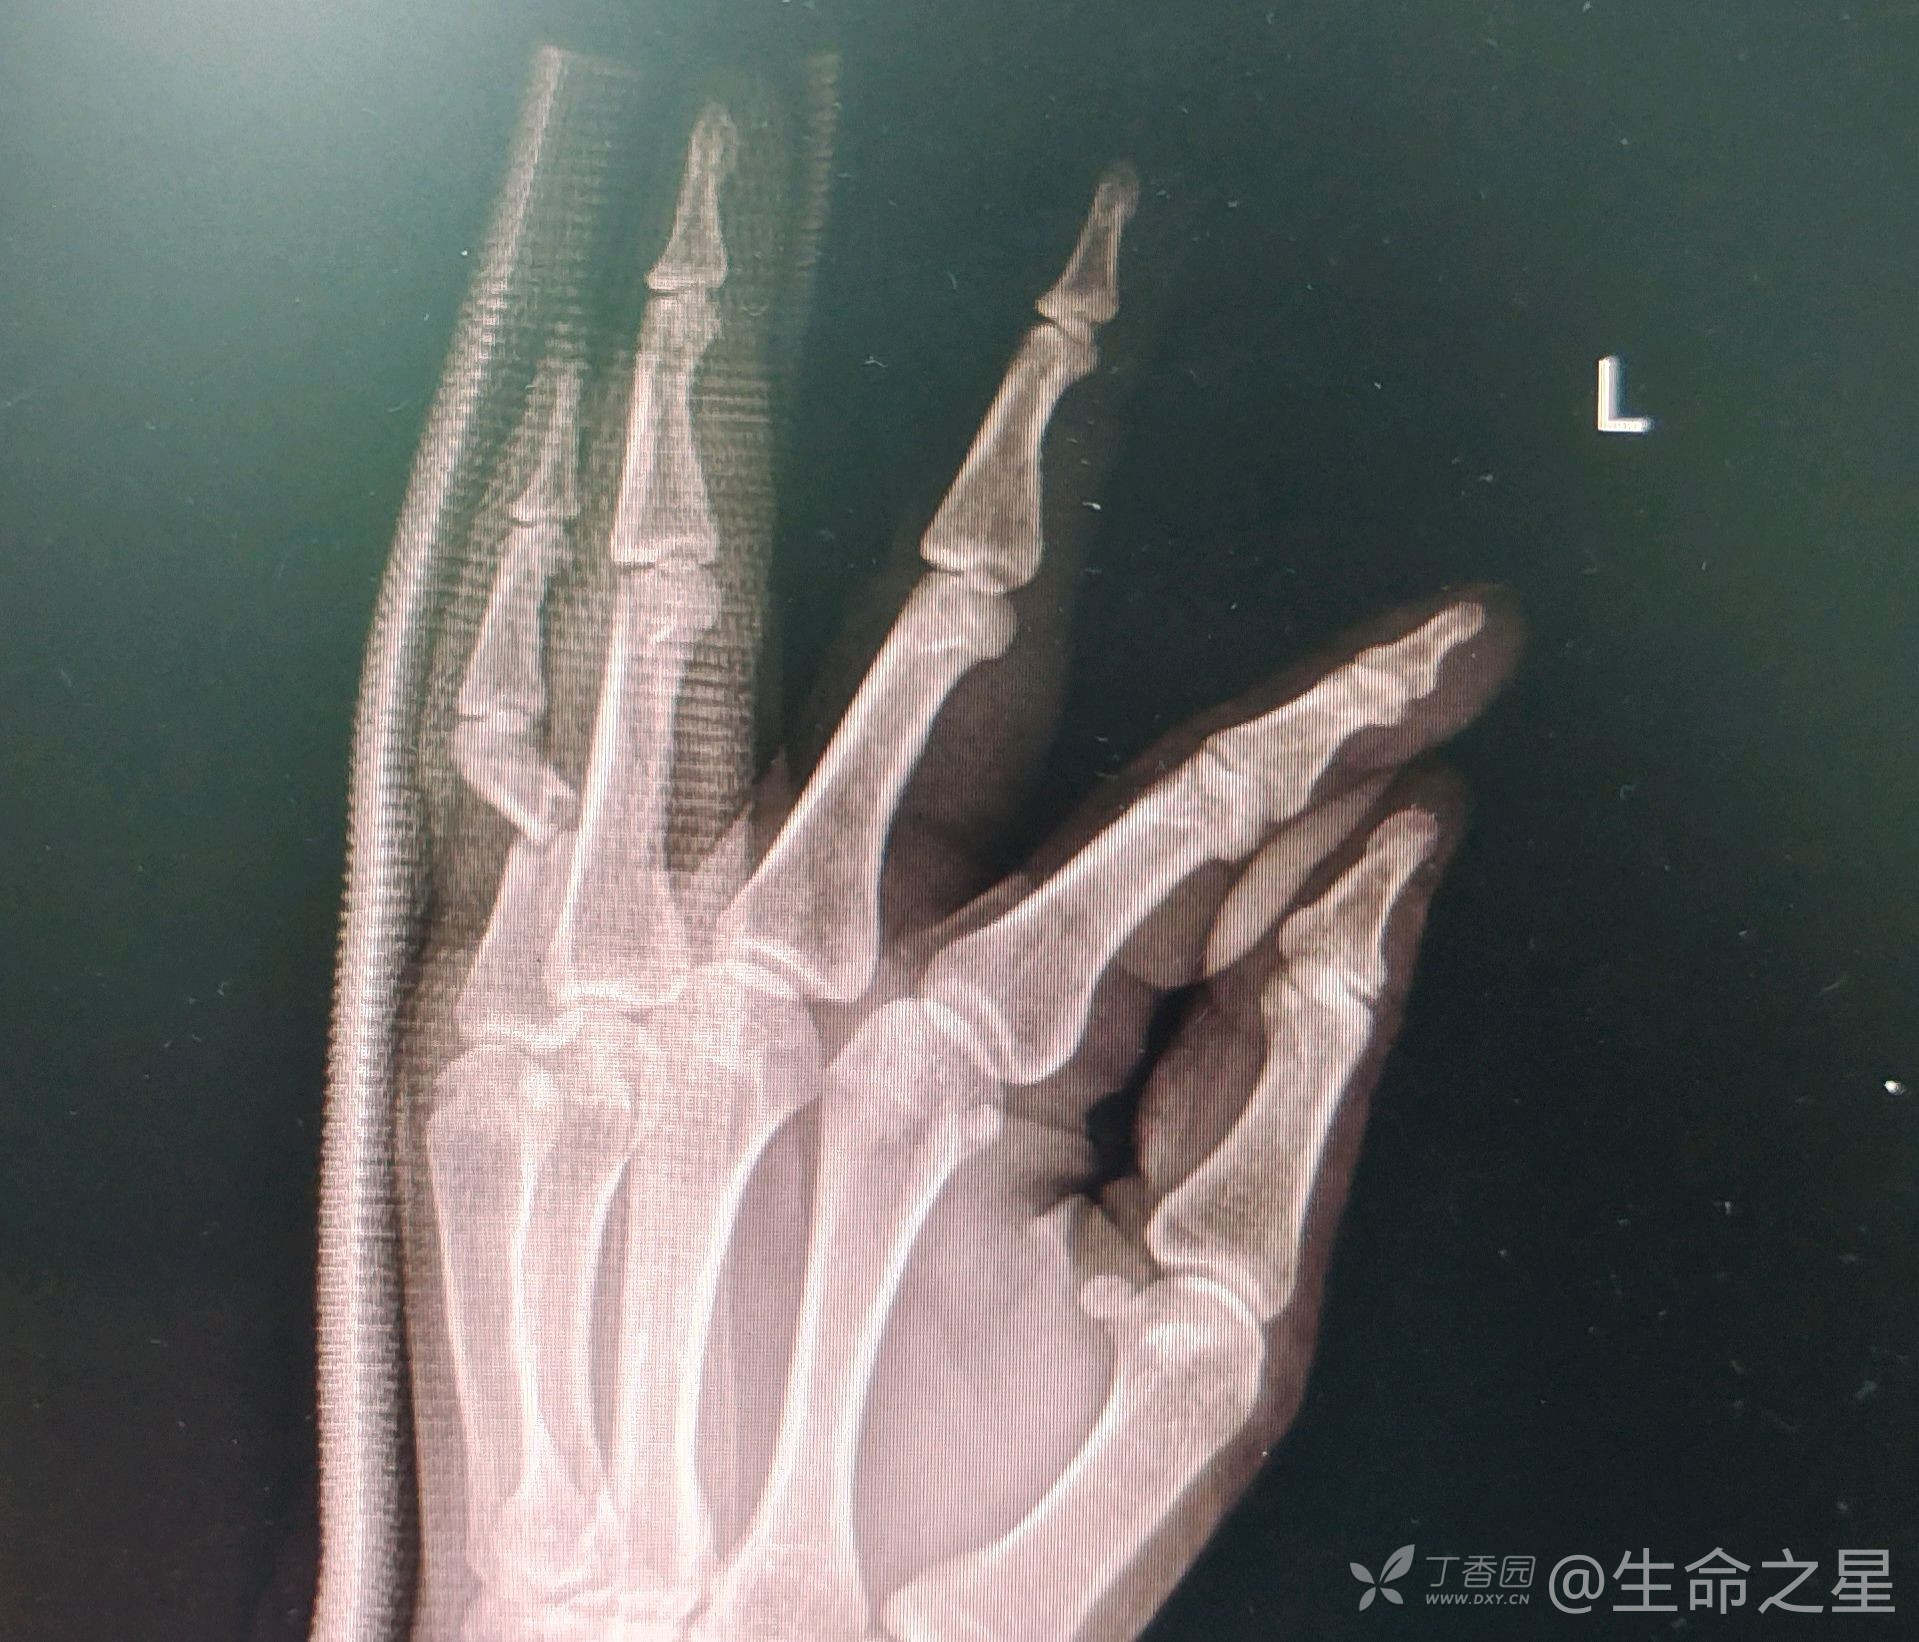

zzf1056 达人已点赞中年男子,重物砸伤致小指疼痛畸形半月余,既往外伤时拍片提示小指近节指骨骨折成角,建议手术,患者拒绝,2周后再次来门诊就诊,收入院

行手术内固定治疗。